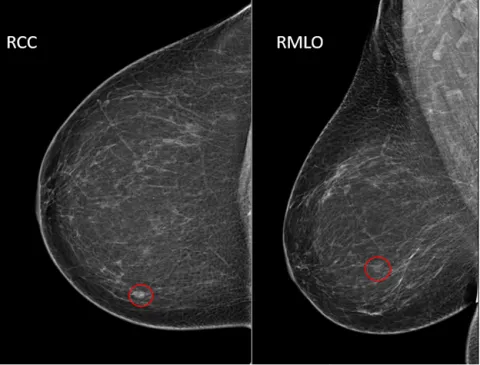

- Standard Views:

- Cranio-Caudal (CC)

- Medio-Lateral Oblique (MLO) - visualizes most breast tissue, including axillary tail.

- Key Malignant Signs:

- Spiculated masses.

- Suspicious microcalcifications (e.g., pleomorphic, fine linear, branching/casting type).

- Architectural distortion.

- Developing asymmetry.